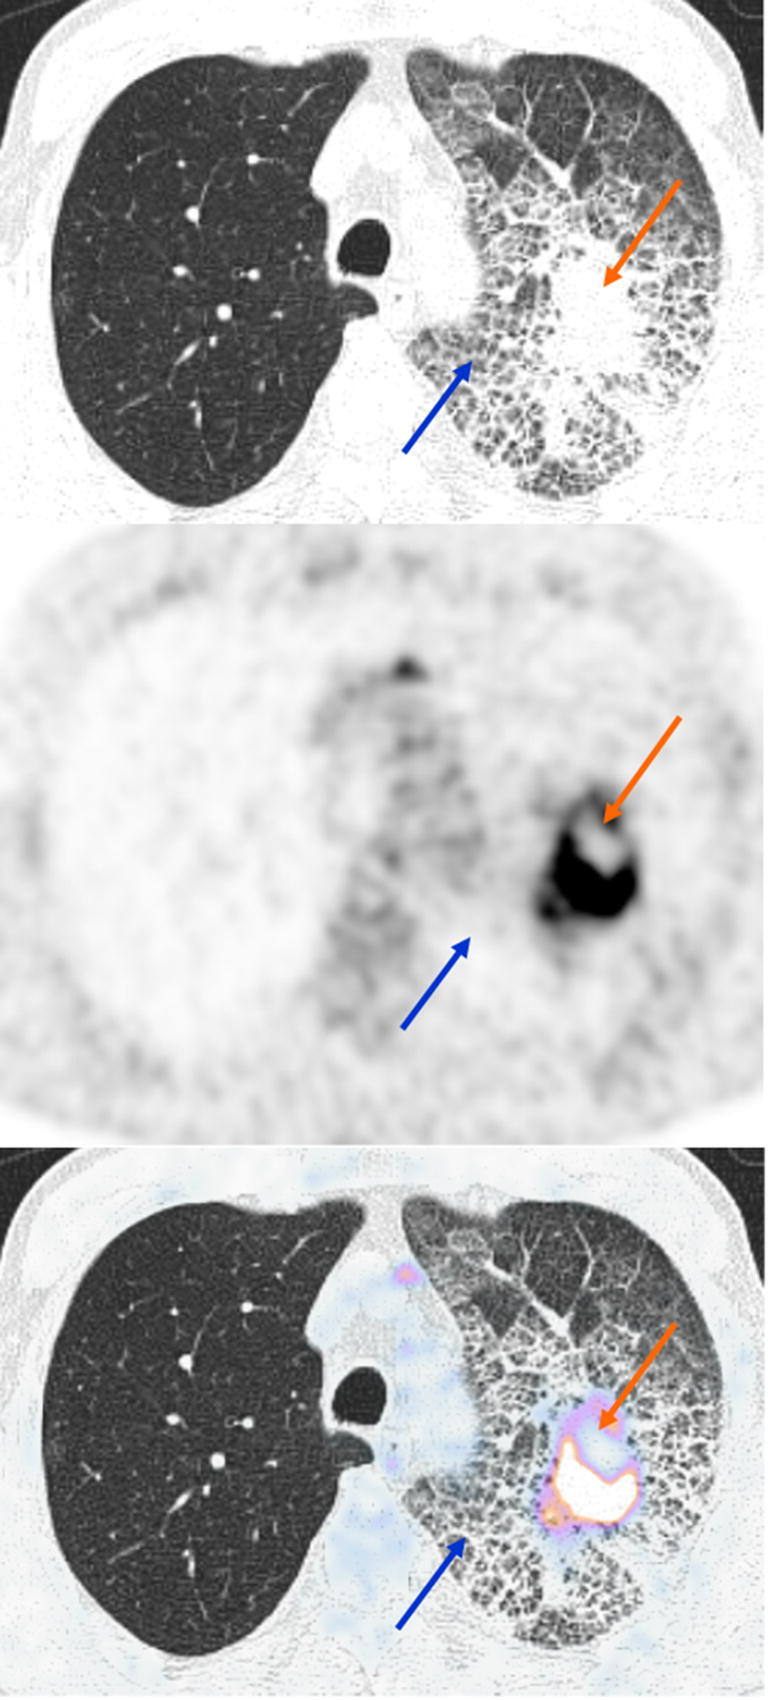

Case 5

A 63-year-old man was referred for 18F-FDG PET/CT for staging of left lung adenocarcinoma. PET/CT confirmed increased FDG uptake of the lung mass and showed minimal FDG uptake of diffuse GGO with superimposed interlobular septal thickening and intralobular lines mostly in the left upper lobe of the lung. This crazy-paving pattern offers a wide range of differential diagnoses, in this context bronchioloalveolar carcinoma or intra-alveolar hemorrhage, and is not specific of COVID-19 infection (Fig. 5).

Fig. 5.

18F-FDG PET/CT (axial CT-upper row, axial PET- middle row, axial fused PET/CT-lower row) showing increased FDG uptake of a lung mass (orange arrow) with minimal 18F-FDG uptake of GGO, interlobular septal thickening and intralobular lines mostly in the left upper lobe of the lung (blue arrow). SUVmax 15.75